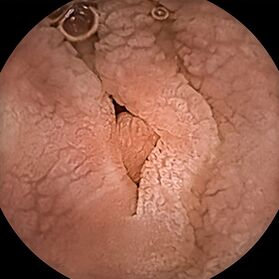

Die verwendete Videokapsel „Kamerapille“ ist eine winzige Digitalkamera, die einschließlich Licht-, Batterie- und Funktechnik nur etwa die Größe eines Gummibärchens hat. Auf ihrem Weg durch den Magen-Darm-Kanal nimmt die Kapsel automatisiert Bilder der Schleimhaut des Verdauungstraktes auf und sendet sie nach außen an einen tragbaren Datenrekorder. Die von uns verwendete neueste Kapselgeneration passt sogar die Bildfrequenz der Geschwindigkeit an, mit der sich die Kamerakapsel im Darm bewegt und kann kleinste Objekte bis zu einer Größe von 0,7 mm erkennen.